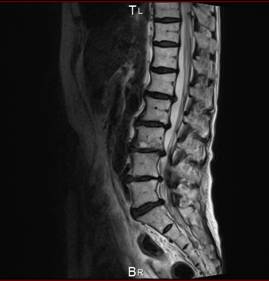

首頚椎椎間板ヘルニア専門HEADLINE

頚椎と腰椎ヘルニア 狭窄症 痛み シビレ 交通事故むち打ち治療自賠責